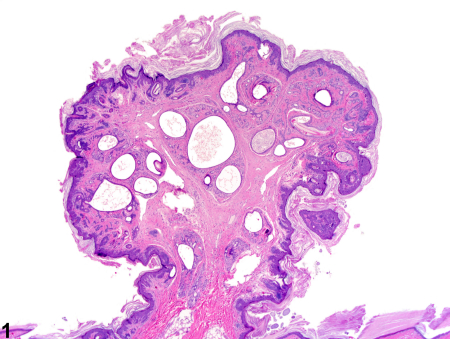

هامارتوما یک تومور غیرسرطانی (خوشخیم) است که از همان سلولهای موجود در بافت اطراف ساخته شده است، اما این سلولها و بافتها به صورت نامنظم و بینظم تومور میکنند. بیشتر هامارتوماها هیچ علامتی ایجاد نمیکنند و جدی نیستند. اگر هامارتوما مشکلی ایجاد کند، معمولاً با جراحی برطرف میشود.

هامارتوما (تلفظ: هَم-آر-تُو-ما) یک تومور شبهتوموری است که میتواند در هر جای بدن ظاهر شود. وقتی مردم کلمه «تومور» را میشنوند، اغلب به سرطان فکر میکنند، اما هامارتوماها سرطان نیستند. آنها فقط ترکیبی از همان سلولها و بافتهایی هستند که به طور طبیعی در آن ناحیه از بدن وجود دارند، اما به صورت نامنظم تومور کردهاند.

8. فرق هامارتوما با آدنوما و لیپوما چیست؟

هامارتوما: ترکیب نامنظم از بافتهای طبیعی همان ناحیه

آدنوما: فقط از یک نوع سلول (معمولاً غددی) و منظمتر

لیپوما: فقط بافت چربی